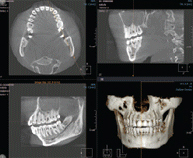

3차원 정밀진단 시스템

얼굴 골격을 빠짐없이 분석합니다

얼굴 골격의 모든 방향을 빠짐없이 촬영하고

치아와 치조골의 상태 및 잇몸뼈의 양과 길이 등의

전반적인 상태를 정확하게 측정하고 진단하여

한치의 오차 없는 시술로 진료의 안정성을 높힙니다.